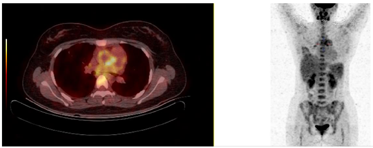

行肺动脉CT提示右肺上叶前段及右肺中叶肺动脉闭塞、右肺动脉干远端及左肺下叶前基底段肺动脉管腔变窄,上述肺动脉供血的肺实质呈现磨玻璃及实变影;正电子发射计算机断层显像示升主动脉管壁环形葡萄糖代谢增高,管壁稍增厚、毛糙。综上,诊断为大动脉炎、肺栓塞不除外。

入院查血常规示白细胞计数为10.0×109/L,中性粒细胞比例为59.7%,血红蛋白为93 g/L,血小板计数为479×109/L,平均红细胞体积为71.9 fl,平均红细胞血红蛋白含量23.0 pg,平均红细胞血红蛋白浓度321.0 g/L。尿便常规、肝肾功能、电解质、心肌损伤标志物均正常。超敏C反应蛋白为78.52 mg/L。同型半胱氨酸为10.30 μmol/L。D二聚体为2.32 mg/L。红细胞沉降率为106 mm/h。降钙素原、血尿免疫固定电泳均阴性。直接抗人球蛋白试验弱阳性。抗核抗体阳性(颗粒型1:100),抗ENA谱阴性。免疫球蛋白A 4.5↑ g/L,补体C4 0.376↑ g/L,免疫球蛋白M、免疫球蛋白G和补体C3均正常。类风湿因子、抗环瓜氨酸肽抗体、抗中性粒细胞胞浆抗体、抗肾小球基底膜抗体、狼疮抗凝物、抗心磷脂抗体、抗β2-糖蛋白1抗体均阴性。抗凝血酶活性、蛋白C、蛋白S活性均正常。双下肢深静脉超声未见血栓。超声心动图示左心室射血分数正常,主动脉瓣中度反流,右心室收缩功能正常,肺动脉收缩压正常。肺动脉CT提示右肺上叶前段及右肺中叶肺动脉闭塞,右肺动脉干远端及左肺下叶前基底段肺动脉管腔变窄(图1);右肺中叶远端胸膜下楔形实变灶,尖端指向肺门、周围可见片状磨玻璃影、内可见充气支气管气相(图2);右肺上叶前段胸膜下可见小片状实变灶伴磨玻璃密度;肺实质病变分布位置符合右肺上叶前段、右肺中叶肺动脉供血区域;升主动脉管壁可疑增厚。正电子发射计算机断层显像(positron emission tomography, PET-CT)示升主动脉管壁环形葡萄糖代谢增高,管壁稍增厚、毛糙(图3),考虑大动脉炎可能大。

本病例旨在提高对TA肺部表现,包括肺动脉受累的认识。患者为青年女性,临床表现为胸痛、咳嗽、咳黄痰、发热,白细胞计数、红细胞沉降率和C反应蛋白升高,胸部影像学可见新发渗出影,被误诊为社区获得性肺炎。但是,应用广谱抗生素足疗程治疗效果不佳。通过D二聚体持续升高、胸部影像学所示胸膜下楔形病灶的特征,进一步行CTPA示多发肺动脉闭塞或狭窄、肺实质病变同病变血管范围一致、升主动脉管壁可疑增厚,进而行PET-CT证实升主动脉管壁环形葡萄糖代谢增高,管壁增厚、毛糙;UCG提示主动脉瓣中度反流。此例患者符合改良的Ishikawa大动脉炎分类标准[2]。此患者的鉴别诊断应考虑到动脉粥样硬化、纤维肌性发育不良及纵隔纤维化。因患者发病年龄早,无高血压、吸烟、糖尿病、血脂异常等动脉粥样硬化的危险因素,可基本除外动脉粥样硬化;同时有慢性贫血病史,血小板计数偏高,红细胞沉降率、C反应蛋白等炎症指标升高,由此可除外纤维肌性发育不良;CTPA未见纵隔及肺门软组织密度影,可除外纵隔纤维化。